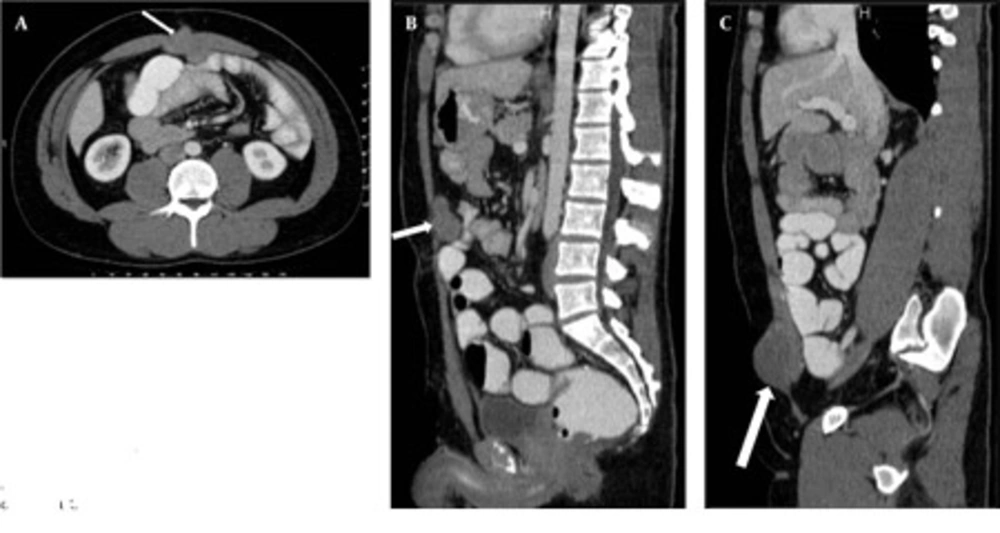

In CTE examination, there was no sign of manifested small bowel obstruction and intraluminal pathology. Intraabdominal solid organs were normal. A 39 × 42 × 36 mm sized contrast material enhancing solid mass was seen between the rectus muscles at the superior region of the umbilicus, invading to the subcutaneous fatty tissue anteriorly and limited by the omentum posteriorly. This mass had a well-defined margin making indentation without invasion to the small bowel loops (Figure 1). Another similar solid mass 60 × 48 × 35 mm in size was seen in the right inguinal region, anterolateral to the right rectus muscle, similarly indentated small bowel loops and limited by the omentum. Adjacent to the posterior segment of the eleventh left rib, a similar solid subcutaneous lesion (approximately 13 mm in diameter) was observed. In addition, another 38 × 33 × 29 mm sized, hyperdense mass with lobulated contour was seen at the small bowel mesentery, being close to the ileal branches of the superior mesenteric artery (SMA). It is observed that, this mass surrounded the SMA branches, but did not cause a significant obstruction in the arterial flow (Figure 2). Small bowel segments close to the defined mass were detected as normal. According to CTE results, this mass was interpreted as a mesenteric DT.

A, Axial cut obtained at the superior level of the umbilicus; B, Reformatted midline sagittal; and C, Right parasagittal CTE images of the patient show anterior abdominal wall desmoid tumors (DTs) (arrows). The relationship between DTs and small bowel loops is clearly seen on the MDCT images.